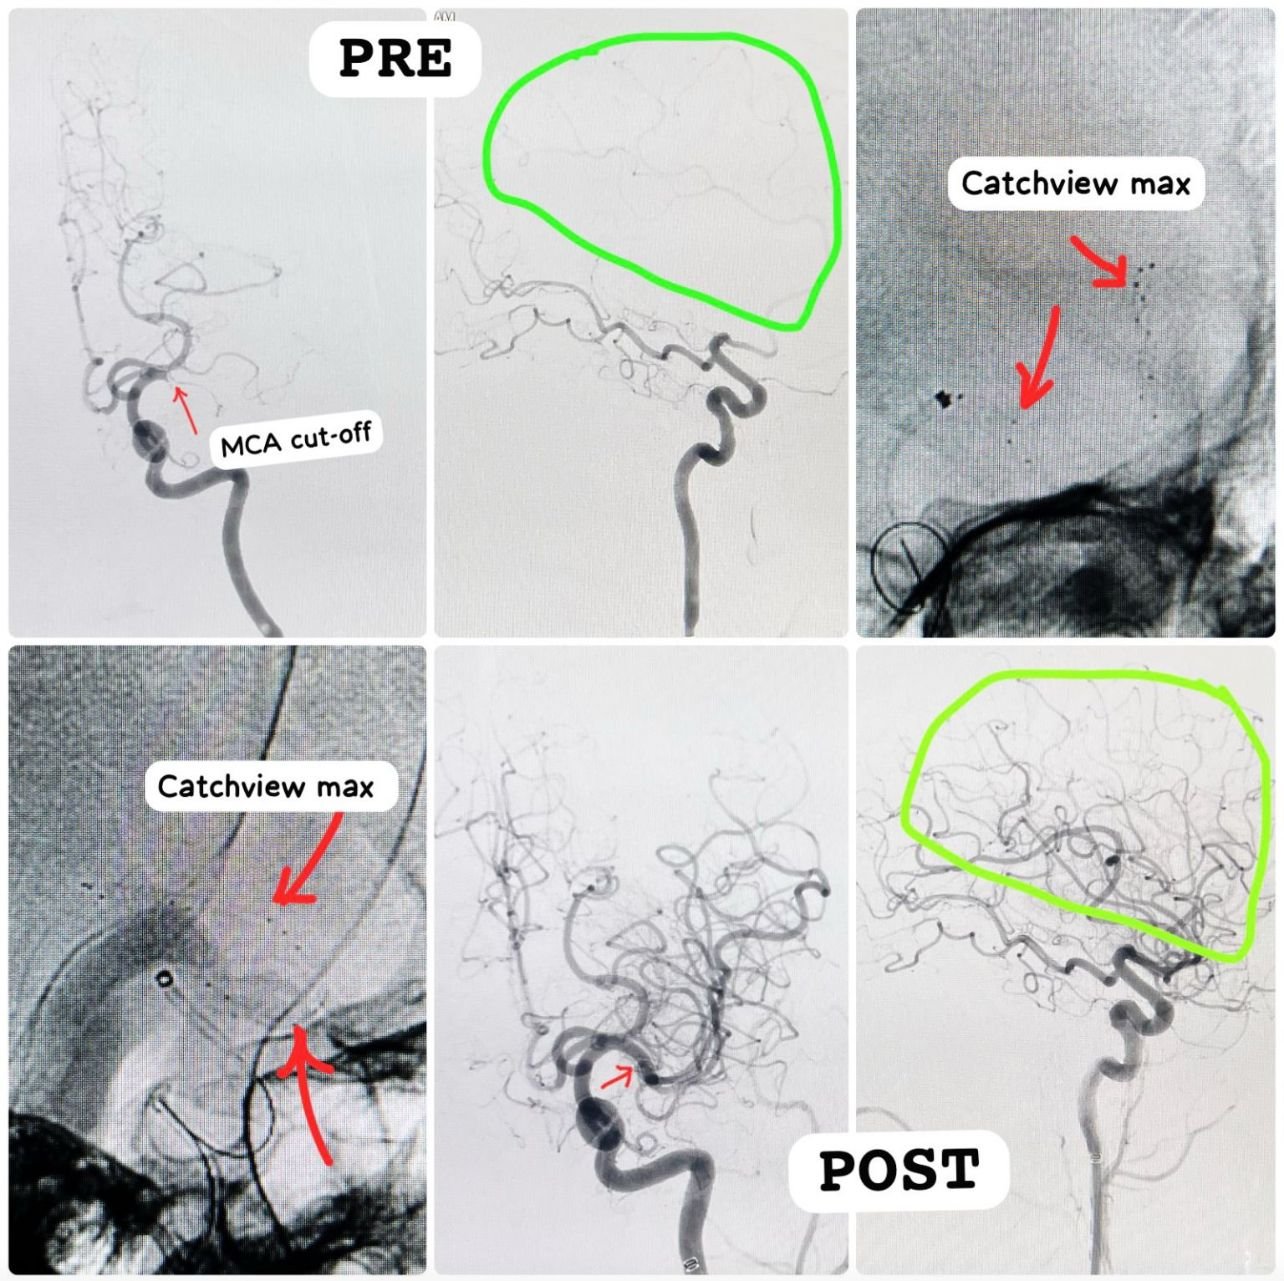

Acute Stroke - Mechanical Thrombectomy